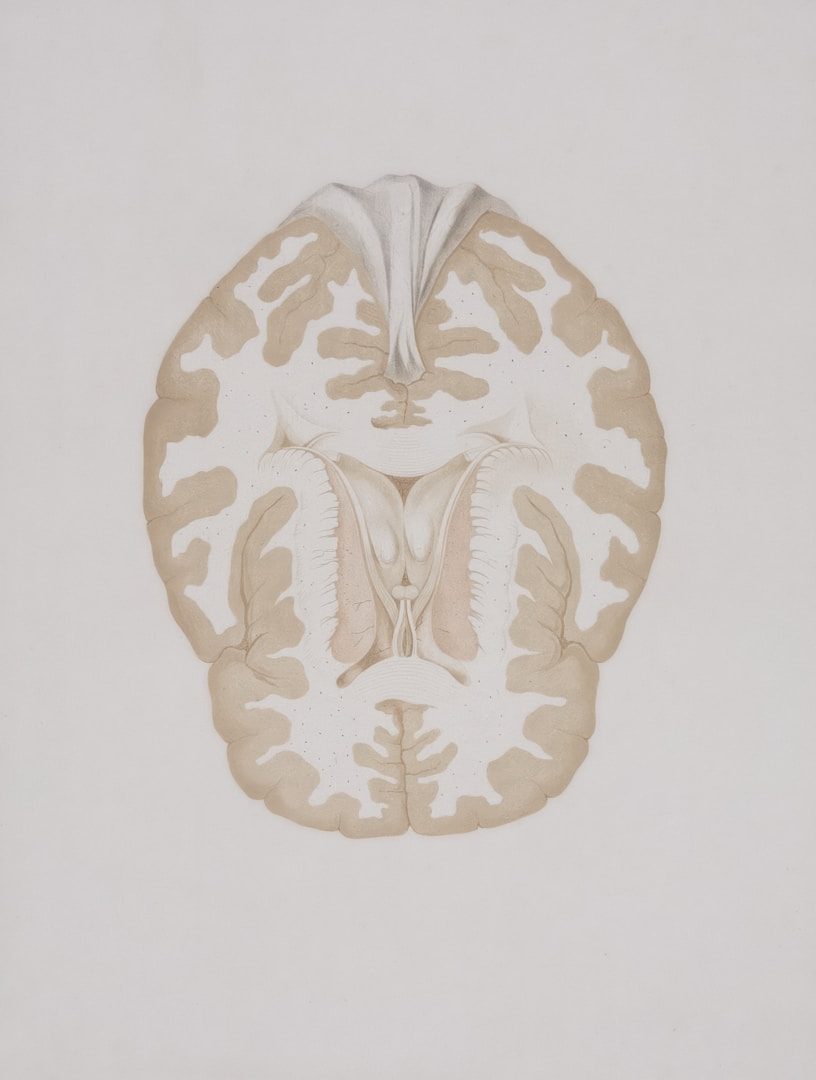

Where Neuroscience Meets Meaning

Neuroscience-Based Methods

Some days, our brain can feel like our worst enemy. How often do we find ourselves talking ourselves out of opportunities, or criticizing ourselves in ways we would never do to another?

Neuroscience has shown that our brains continue to change throughout our lives. As such, you are not doomed to endlessly repeat patterns of behavior that no longer not serve you.

We use the latest understanding of brain function to help you move past self-imposed blockages, quiet the inner critic, and help build a stronger belief in yourself, supporting lasting change.